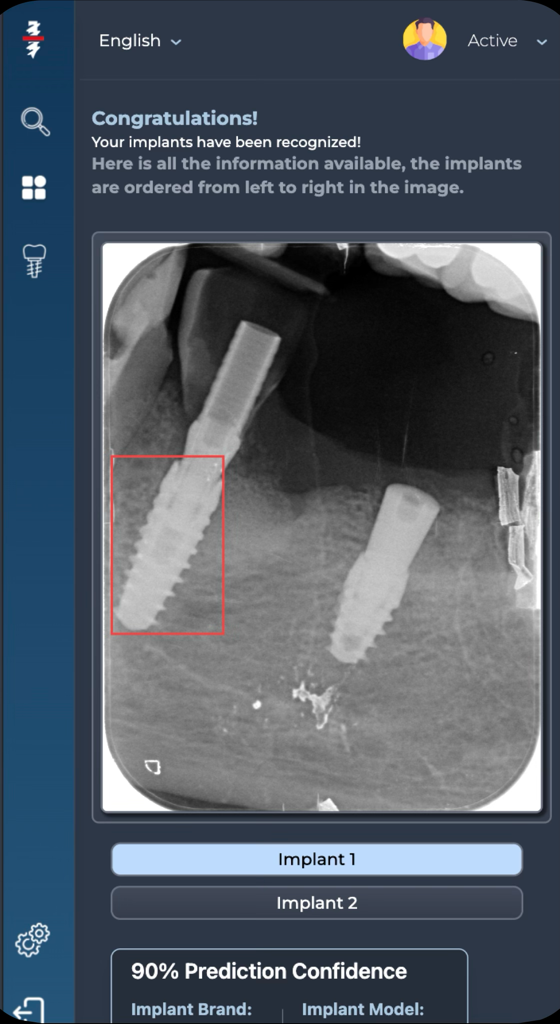

Cloud-based virtual assistant for dental professionals

Automatic processing of digital dental data using Artificial Intelligence.